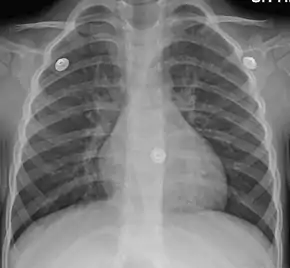

Mild peribronchial cuffing as seen in viral bronchitis